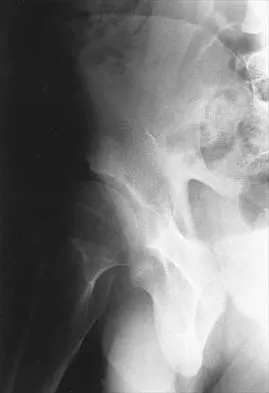

A patient with severe rheumatoid arthritis reports progressive hip pain. Serial hip radiographs will most likely show which of the following findings?

Explanation

Radiographic findings in patients with rheumatoid arthritis include symmetric joint space narrowing, periacetabular and femoral head erosions, and diffuse periarticular osteopenia. In advanced stages, protrusio acetabuli is a common finding. Ranawat and associates have shown a rate of superior femoral head migration of 4.5 mm per year and medial (axial) migration of 2.5 mm per year. Asymmetric joint space narrowing is a classic radiographic finding of degenerative arthrosis. Sacroiliac joint ankylosis commonly occurs in ankylosing spondylitis. Hip synovitis is a pathologic diagnosis, not a radiographic finding. Lachiewicz PF: Rheumatoid arthritis of the hip. J Am Acad Orthop Surg 1997;5:332-338.